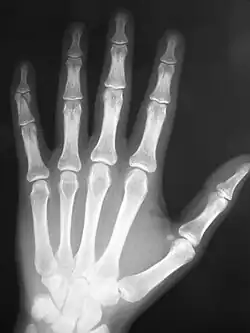

On November 8, 1895 Wilhelm Conrad Röntgen discovered x-rays by chance while investigating cathode rays, effectively laying the foundation for the medical discipline of radiology. This discovery would grow to include various methods of imaging and establish itself as a crucial element of modern medicine. November 8 was eventually chosen as the appropriate day to mark the celebrations which are observed by radiological societies the world over.[2]